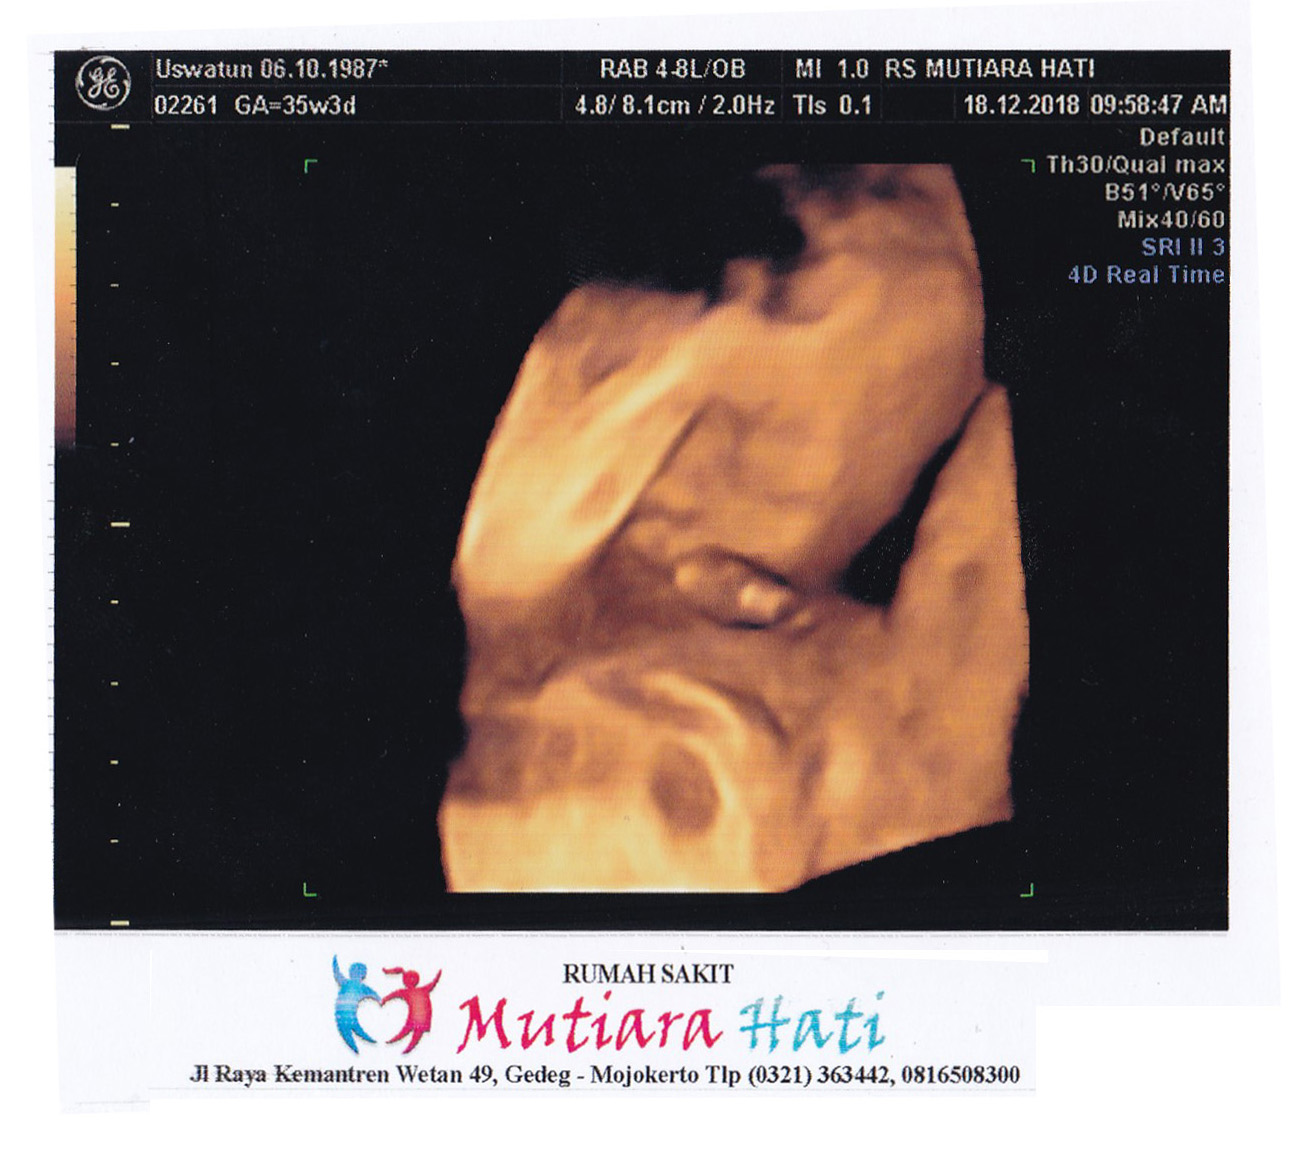

Gambar Usg 6 Bulan

Kenali Cara Membaca Hasil USG Untuk Tahu Kondisi Bayi - Ibupedia Bagaimana Cara Membaca Hasil USG? • Hello Sehat Pergerakan Janin umur 6 bulan!!! Hasil USG - YouTube USG 3D HAMIL 25 MINGGU ( 6 bulan) | SEHAT SELALU CALON ANAKKU - YouTube 5 Langkah Membaca Hasil USG yang Bisa Bunda Pelajari Ini Dia Cara Membaca Hasil USG dengan mudah - Mamapapa.id % Story of My Journey: USG Kehamilan 6 Minggu Cara Membaca Hasil USG yang Benar, Wajib Tahu! Ini Rata-Rata Berat Janin 5 Bulan - Alodokter usg 6 minggu USG 4 Dimensi Kehamilan Halaman 1 - Kompasiana.com Penyebab janin dalam kandungan menghilang USG 4 Dimensi 6 bulan 2 Minggu - YouTube Penjelasan di Balik Bayi Bisa Tersenyum di dalam Kandungan janin 6 bulan hamil 6 bulan kehamilan 6 bulan perkembangan https://babyologist.com/blog/mengapa-bayi-lebih-aktif-di-malam-ha… | Tips, Gynecology, Pandora screenshot USG [2] : Enam Belas Minggu Enam Hari – Jejak-jejak yang Terserak Kapan Denyut Jantung Janin Bisa Terdeteksi? | HonestDocs USG 4 Dimensi Kehamilan Halaman 1 - Kompasiana.com USG Pertama Kehamilan 6 Minggu | KISAH KASIH BUNDA USG 2 Dimensi janin umur 6 bulan - YouTube Usg hamil 6 week 4 day (menurut usg) 6week 5day (menurut hph USG [6] : 34 Minggu 2 Hari – Jejak-jejak yang Terserak foto 4 D kehamilan 6 bulan dg usg… - salsabila obgyn clinic | Facebook Cara Membaca Hasil USG yang Benar, Wajib Tahu! banyak yg mengalami ga? 7 minggu usg belum terluhat janin sama sekali hanya - IbuHamil.com Ukuran Kantong Janin 6 Minggu Yang Normal Dan Tidak Bermasalah - Hamil.co.id ALBUM KELUARGA: USG 4 DIMENSI BAYI 6,5 BULAN (ADIK DZIKRI) Informasi Kehamilan Sehat Bulan 6 : Perlukah USG 3 dan 4 Dimensi? - Semua Halaman - Nakita Tiga Hal yang Jarang Orang Ketahui jika Ibu Hamil Lakukan USG 4D - Tribun Jabar usg 6 bulan 3 dimensi 12 Oktober 2016 - YouTube Gambaran Hasil Usg Kehamilan 5 Minggu Yang Perlu Diperhatikan - Hamil.co.id share hasil usg uk 6 bulan ? - IbuHamil.com Begini Kondisi Janin di Usia Kehamilan 1 sampai 6 Minggu Kehamilan - Tribun Sumsel USG 3D dan USG 4D, Apa Bedanya? Mana yang Lebih Baik? 6 Hal yang Harus Dipersiapkan saat Pertama Kali Melakukan USG | Popmama.com Evan Reisha - Kontrol Kandungan Ke-6 (Trimester 2-3, 27W6D) JANIN BELUM TERLIHAT SAAT USG? JANGAN KHAWATIR, MOMS! - susistory Lakukan USG Saat Trimester Kedua, Mama Bisa Tahu 6 Hal Penting Ini | Popmama.com Manjakani Kanza Asli Aceh: Hasil Usg Usia Kehamilan 6 Bulan Inilah Alasan Ibu Hamil Perlu Melakukan USG Kehamilan Hasil USG 6 bln, JK cewe??? - IbuHamil.com Perkembangan Kehamilan Si Kembar 15 Minggu 5 Hari – cizkah.com Tag: bayi - Ngeri! Pedofil Incar Janin Belum Lahir, Bukti Foto USG Gegerkan Pengadilan - Tribun Manado Pentingkah USG 4 Dimensi? - Mommies Daily USG [1] : Enam Minggu Lima Hari – Jejak-jejak yang Terserak Usg 4D 25 minggu/ 6 bulan. IT’S A BOY!! - YouTube Cara Melakukan USG 2 Dimensi yang Benar dan Tepat - Bidanku.com Cara Membaca Hasil USG, Simak Ini Panduannya Viral, Rekaman USG Bayi Kembar Bertengkar dalam Rahim - Citizen6 Liputan6.com Pengalaman Hamil Kembar - The Urban Mama Hamil Setelah Keguguran - Mommies Daily Janin 6 Bulan : Tumbuh kembang - Yang perlu dilakukan (Kerjanya) Jumlah Bayi Kembar yang Lahir Tak Sesuai Hasil USG? Ini Penjelasan Dokter Gambaran Hasil Usg Kehamilan 6 Minggu Yang Normal - Hamil.co.id Diary Kehamilan: Cerita Kehamilan Pertama, Pertama Tahu Hamil – ranselriri Aryani Fitriana Umumkan Hamil Anak Kedua Lewat Foto Hasil USG! - Semua Halaman - Nakita Catatan Calon Ayah # 6: USG Kehamilan | WebLog Andika Priyandana Hasil USG 4 Dimensi Ini Menyeramkan - Health Liputan6.com Wajah & Kelamin Bayi 6 Bulan - Halaman 2 - IbuHamil.com USG 4 Dimensi Kehamilan Halaman 1 - Kompasiana.com Pamerkan Perut Rata Saat Hamil 6 Bulan, Kisah Wanita Ini Viral - Parenting Fimela.com Adib’s Mom: USG 4D Usia Kandungan 6 Bulan Kehamilan Bulan Keenam | New Mom’s Diary 10 Fakta Janin 37 Minggu Yang Harus Diketahui Oleh Calon Ibu - Cintai Hidup USG 4D - Video Perbedaan USG 4D, 3D dan 2D yang Perlu Anda Ketahui | theAsianparent Indonesia PT. Setia Manggala Abadi : “Hasil pengambilan USG dengan usia kehamilan ibu 6 bulan. Pengambilan gambar USG menggunakan USG SOGATA SG9 4D & Color Doppler #sogata… https://t.co/pDqV007DiP” Cara Membaca Hasil USG, Simak Ini Panduannya 6 month Pregnancy | Blognya Ayu USG Janin 6 Bulan - 25 Minggu. Kelihatan Wajah & Jenis Kelamin. - YouTube Pengalaman saat Alami Kehamilan Kosong (Blighted Ovum) Halaman all - Kompasiana.com Perempuan Ini Mengaku Hamil 6 Bulan di Usia 70 Tahun Halaman all - Kompas.com Tahap Perkembangan Hamil 6 Bulan | Redaksi Cepat FDA Peringatkan Ibu Hamil Jauhi USG Buat Kenang-kenangan - Health Liputan6.com Masa Perkembangan dan Posisi Janin Usia 6 Bulan | Prenagen 6 bulan – Masrafa.com 3 Cara Membaca Hasil USG yang Benar, Biar Nggak Salah Kaprah | merdeka.com Story of My Journey: USG Kehamilan 19 Minggu Hamil 5 Minggu: Pentingnya Pemeriksaan Kandungan dan USG RutinElla | MamiBuy Janin 6 Minggu Ini Berpose Jari V - Sriwijaya Post Ini Waktu Yang Ideal Untuk Melakukan USG 4 Dimensi Saat Hamil - Semua Halaman - Nakita Sedang hamil, ini 10 foto USG yang kerap dipamerkan Shandy Aulia Moms, Ini Penyebab dan Tanda Hamil Bayi Berukuran Kecil - kumparan.com Membaca hasil USG pada pemeriksaan kehamilan | Darwis untuk Indonesia Kehamilan 23 Minggu | KISAH KASIH BUNDA Foto: Perkembangan Janin dalam Kandungan dari Bulan ke Bulan - kumparan.com Keluarga JagoAN: Kehamilan Bulan ke 6 (Minggu ke 21 - 24) USG 4 bulan – pratiwanggini.net Kapan Ibu Hamil Sebaiknya Melakukan USG? USG 4D - Video Perbedaan USG 4D, 3D dan 2D yang Perlu Anda Ketahui | theAsianparent Indonesia USG 6 bulan kehamilan ||cewek/cowok…??? - YouTube Sharing Hasil USG 6 bulan - IbuHamil.com Cari Tahu Berat Janin 6 Bulan yang Normal di Sini - Alodokter Ciri Kehamilan 6 Minggu Yang Sehat, Harap Hati-hati Mandi Air Hangat! Netizen Peringatkan Shandy Aulia Karena USG Tiap Minggu, Bahayakah? Manfaat USG untuk Ibu Hamil dan Janin - Ibupedia Usg 4 dimensi, Klinik Metro Medika di perumahan Metro Permata I, jl Metro Permata utama blok E2 no 3 karang tengah, Ciledug., Tangerang (2020) Dinamika Hidupku: Oktober 2013 Aneh, Hamil 6 Bulan Perut Perempuan Ini Tetap Rata Kehamilan Pertamaku – Persiapan Calon Ibu Menjelang 7 Bulan - F-News Kehamilan 6 Bulan: Keluhan Apa yang Anda Rasakan?